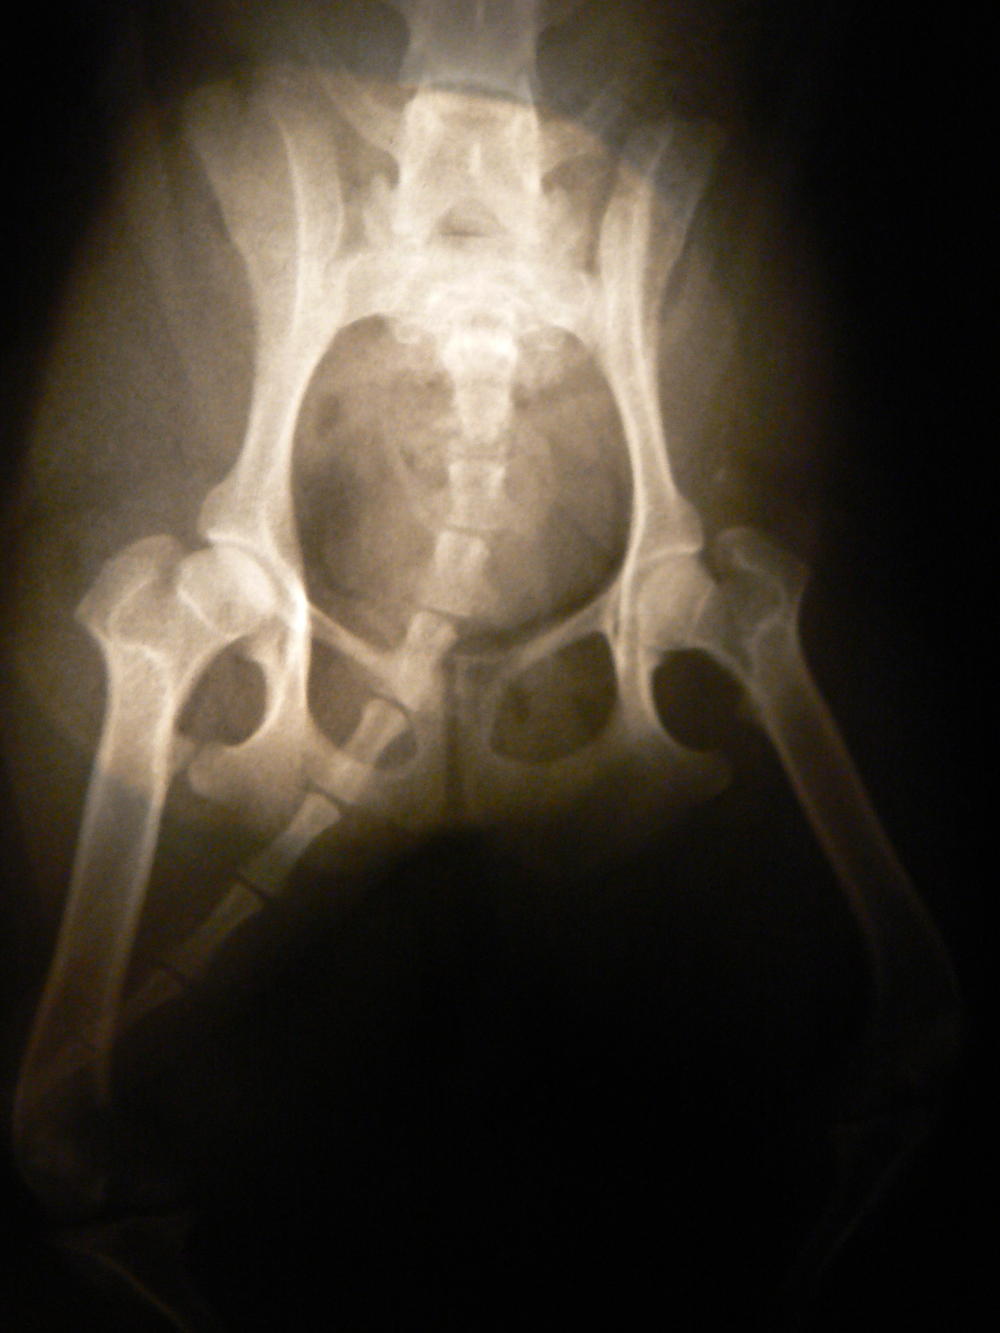

yamagutti, посмотрите пожалуйста на наш снимок. Проблема описывалась в теме"Подпрыгивает при ходьбе" Нам сказали, что с коленями все нормально, а вот с бедренными суставами - нет. Не знаю,что делать - т.к. сложилось впечатление, что врачи сами толком ничего не видят и не находят

Да в суставе есть изменения, дефартроз, а может быть и некроз головки бедра.

Честно, я не травматолог. По снимку можно только предполагать, а он к тому же низкого качества.

Окончательный диагноз должен ставить он, при этом собачку надо еще и пощупать.

Я думаю, Вам нужно в Москве найти специалиста.